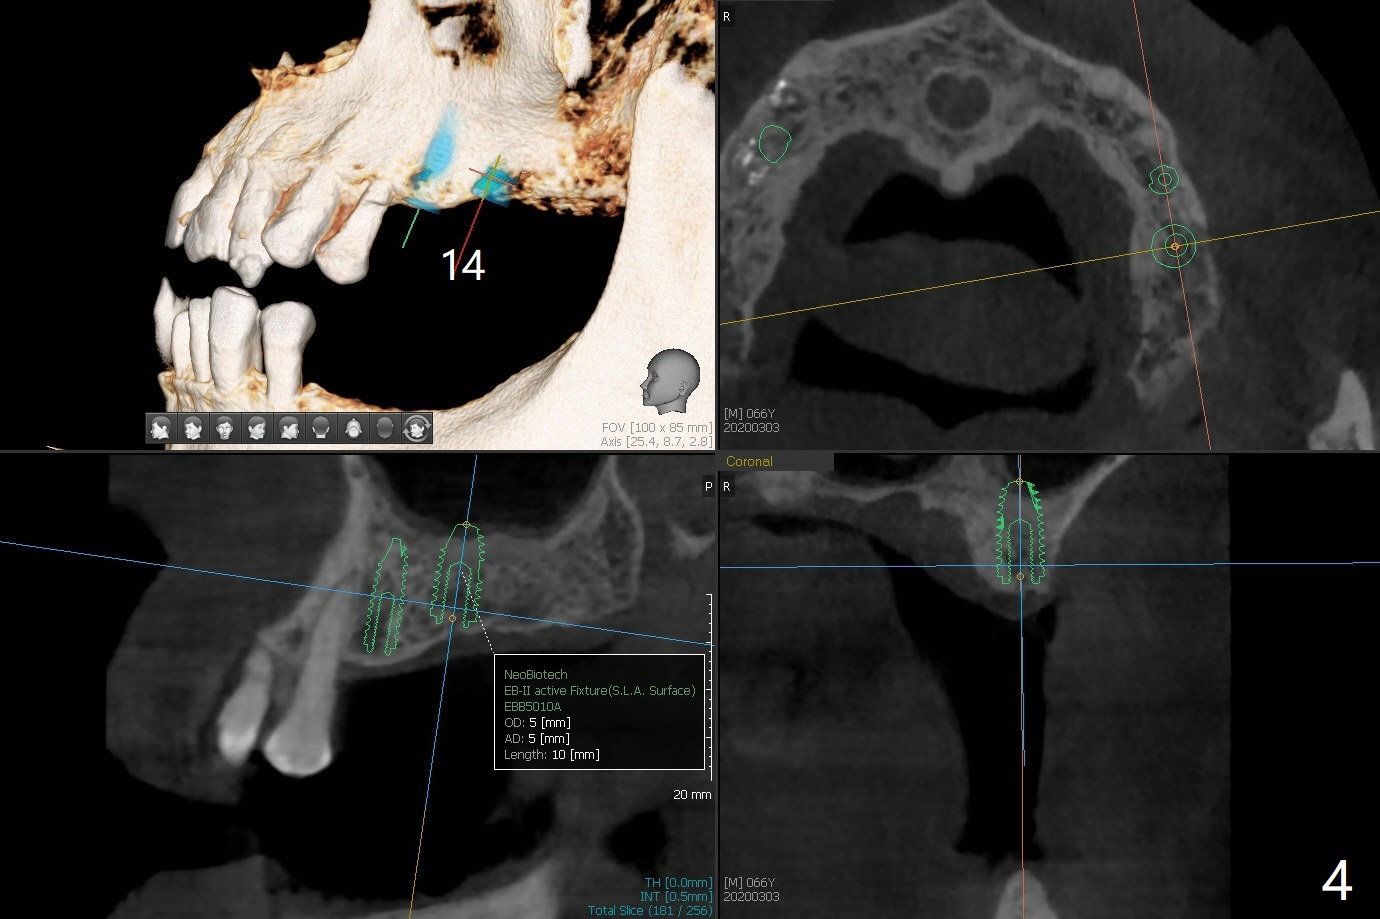

A 66-year-old man has lower RPD. Masti-cation is difficult due to #4 root fracture and #13 and 14 missing (Fig.1). After extraction of #4 with socket antibiotic treatment (Fig.2), finish #13 and 14 osteotomy and implant placement (Fig.3,4). Save auto-genous bone from #13, 14 and #4 using suction trap for #4 buccal gap closure.